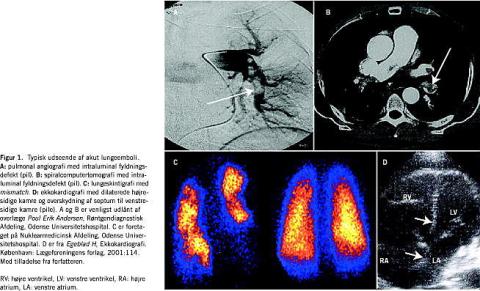

PA anses af mange for at være referencestandarden ved ALE [13-15], selv om metodens sensitivitet og specificitet ikke er optimal under alle omstændigheder [13, 16]. PA er ikke alment tilgængelig, fordrer høj ekspertise og er ikke uden risiko [17, 18], idet undersøgelsen nødvendiggør højresidig hjertekateterisation, og fordi kontrastindgift i sjældne tilfælde kan forårsage allergi og nyresvigt [19, 20]. Diagnosen stilles over-vejende ved påvisning af en intraluminal fyldningsdefekt (Figur 1A ) [21]. Stråledosis er gennemsnitlig 28 mSv pr. undersøgelse [22]. Til sammenligning udgør baggrundsstrålingen i Danmark 3 mSv pr. år.

sCT er mange steder tilgængelig døgnet rundt. Undersøgelsen er minimalt invasiv og kan bidrage til, at der stilles andre diagnoser, men kontrastindgift kan som ved PA forårsage allergi og nyresvigt [19, 20]. Ligesom ved PA baseres diagnosen overvejende på fund af en intraluminal fyldningsdefekt (Figur 1B ) [21]. Den gennemsnitlig stråledosis er 6,4 mSv pr. undersøgelse [22].

LS er som sCT minimalt invasiv, men er ofte ikke tilgæn-gelig uden for dagtid. Modsat forholdene ved sCT og PA er nyresvigt ingen kontraindikation, da der ikke indgives røntgenkontrast. Få andre diagnoser, f.eks. venoarteriel shunt, kan påvises, men i øvrigt er LS ikke anvendelig differentialdiagnostisk. Undersøgelsen udføres ofte som kombineret perfusions- og ventilationsskintigrafi. Det skintigrafiske fund ved ALE er en perfusionsdefekt (Figur 1C ) [21]. Mismatch er betegnelsen for bevaret ventilation i det perfusionsdefekte område, mens match betegner ophævet perfusion og ophævet ventilation i samme område af lungen. Dette anvendtes sammen med defekternes antal og størrelse i the Prospective Investigation of Pulmonary Embolism Diagnosis (PIOPED) til opstilling af en række diagnostiske kategorier, der angav sandsynligheden for ALE med PA som referencestandard [13]. Effektiv dosis for perfusionsskintigrafi er 2,2 mSv. Ved ventilationsskintigrafi afhænger strålebelastningen af metoden, men den er væsentligt mindre end ved perfusionsskintigrafi [23].

EK kan bruges bedside , er alment tilgængelig, giver mulighed for differentialdiagnostik og har ingen kontraindikationer. Undersøgelsen udføres transtorakalt eller transøsofagealt. Diagnosen stilles indirekte ved påvisning af akut cor pulmonale (Figur 1D ) eller mere direkte, om end væsentligt sjældnere, ved visuel erkendelse af en central embolus [24].